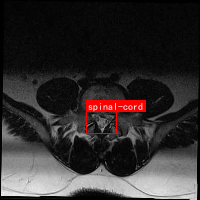

图1展示了脊髓MRI数据集中的样本图像及其对应标注。从图中可以看出,脊髓在MRI图像中呈现为较暗的管状结构,周围是较亮的脑脊液。准确识别和定位脊髓区域对于后续的临床诊断和治疗规划具有重要意义。